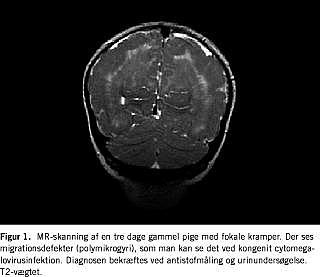

Med MR-skanning har man unikke muligheder for at afklare årsagen til cerebral parese. Med MR-skanning kan man meget sikkert differentiere imellem migrationsdefekter (Figur 3 ) og anoksiskader opstået sent antenatalt eller perinatalt i form af porencefali og periventrikulær leukomalaci.

Centralnervesystemets udvikling kan som bekendt groft inddeles i seks faser, neurolations-: kanalisations-, proliferations-, migrations-, organisations- og myeliniseringsfasen, hver med sine karakteristiske udviklingsanomalier. De hyppigst forekommende luknings- og kanalisationsanomalier, encefalocele, myelomeningocele, Dandy-Walker-malformation og holoprosencefali volder ikke de store diagnostiske vanskeligheder og kan afsløres ved både CT og MR-skanning [1]. MR-skanning er dog at foretrække i disse udredninger, da man ved CT har svært ved visuelt at erkende fossa posterior- og midtlinjeforandringer detaljeret, og man med MR-skanning i modsætning til CT kan afsløre, om der er ledsagende udviklingsforstyrrelser i faserne 3-6. Ud fra de strukturelle forandringer kan man fastslå tidspunktet for en eventuelt udefrakommende påvirkning. Er udviklingsforstyrrelsen betinget af en genetisk defekt, vil der ofte ske en påvirkning af flere faser i hjernens udvikling, hvilket resulterer i, at der eksempelvis både er migrationsdefekter og myelinforandringer [2]. Typeinddeling af migrationsdefekter, hvilket kun er muligt at foretage med MR, er essentiel i den neuropædiatriske udredning. Dels er migrationsdefekter hyppigt forekommende ved mental retardering, epilepsi og cerebral parese, dels er nogle mønstre syndromspecifikke [2].